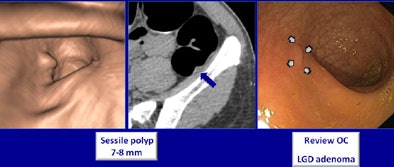

VC did well, and so did the teleradiology scheme. Compared with conventional optical colonoscopy, CTC showed sensitivities in the high 90s, well above those of conventional optical colonoscopy, according to a presentation at the recent RSNA 2011 meeting in Chicago. In addition, CTC had far fewer false positives compared with optical colonoscopy.

In all, nine patients had areas of nontagged stool (1.8%), and three patients had segments with poor distention (0.6%). All files were successfully transmitted. CTC and optical colonoscopy revealed 88 polyps that were 6 mm or larger in 69 patients, the team found.

Based on results from both exams, including repeated colonoscopy exams when necessary, CTC actually beat out optical colonoscopy in two areas: Sensitivity for detecting adenomas 6 mm and larger was 98% sensitivity for CTC versus 90% for optical colonoscopy, and sensitivity for detecting advanced neoplasia was 100% for CTC versus 91% for colonoscopy. The calculation takes into account six missed lesions plus 14 lesions confirmed at repeat CTC -- 14 of the 20 lesions that colonoscopy missed were in the right colon, where colonoscopy has traditionally done a poorer job.